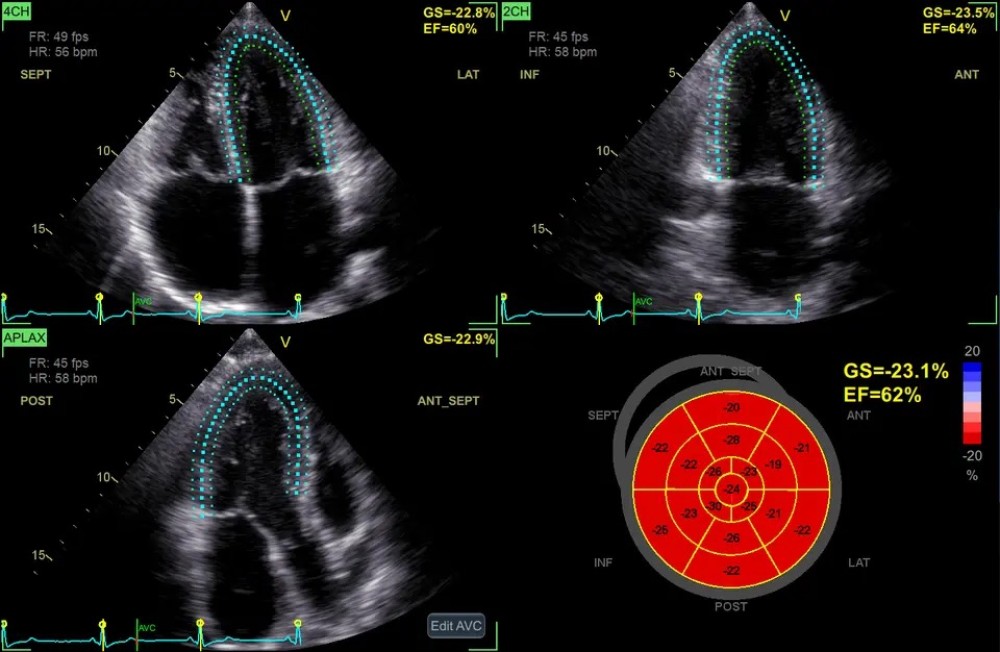

AFI (Automated Function Imaging) – avtomatik funksional görüntüləmə

Açıqlama

Yeni proqram təminatı, məlumatları ekranda göstərilmədən əvvəl emal edir, artefaktları süzgəcdən keçirir və görüntünü daha aydın edir. GE Vivid E90 sistemi, əlavə nəzarət üçün 12 düymlük toxunma ekranı ilə birlikdə 22 düymlük yüksək çözünürlüklü OLED monitor ilə təmin olunur